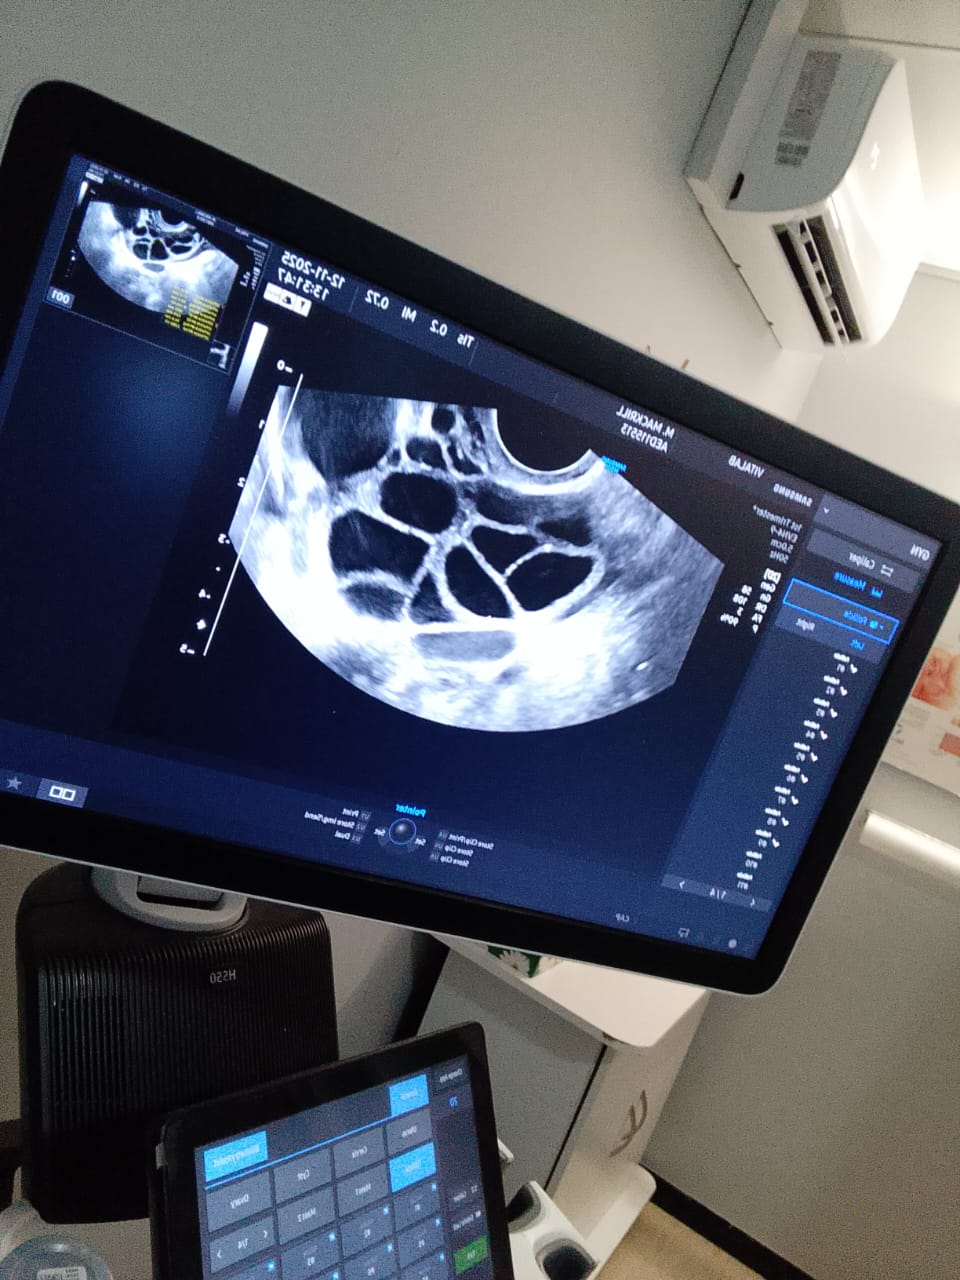

Monitoring Scans

I had a couple of quick visits to the clinic (Vitalab -Sandton) for internal ultrasounds. These checked how my follicles (the sacs containing the eggs) were developing. Seeing the progress gave me a wonderful sense of purpose this gave me hope, positivity for the recipients.